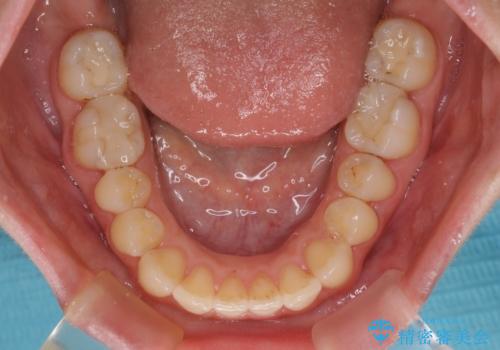

【モニター】オープンバイトをインビザライン矯正で治す

- 前歯の開咬を気にして来院された患者様です。

開咬の治療は、前歯を閉じるように動かすとともに、上下臼歯を圧下(骨内にめり込ませる)させることで進めて行きます。

インビザラインは臼歯の圧下を効果的に行えるため、インビザラインを用いて矯正治療を行うこととしました。

オープンバイトは舌の突出癖により誘発され、治療後も突出癖が残っている容易に後戻りしてしまいます。

治療期間を短縮するためにも、舌突出癖の改善が極めて重要となります。